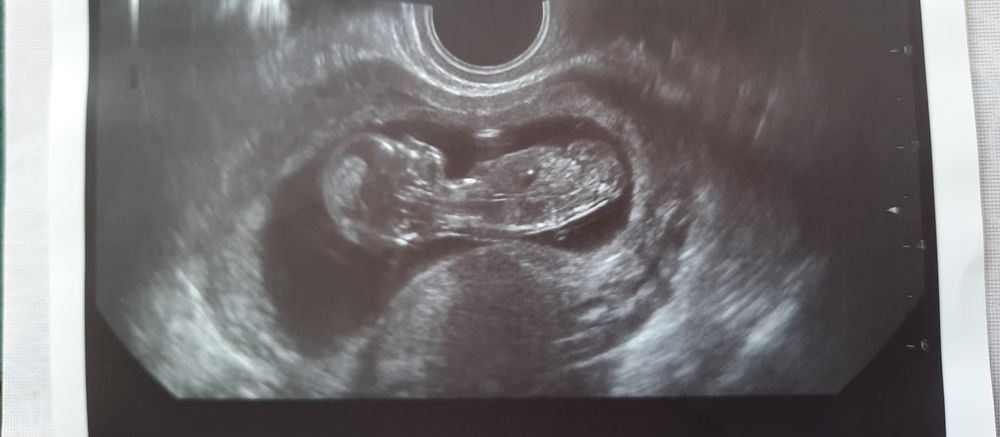

Арина Арина в Благополучная беременность 4 года Гадание по узи))) Пол малыша Как думаете, мальчик или девочка?) Посмотрите еще 20 записей на эту тему Отменить Ответить Таня Девочка) 08.09.2021 Ответить Клюква Реально гадание) пальцем в небо) я вижу ребёнка😜 07.09.2021 Ответить Кристина Я думаю девочка. 07.09.2021 Ответить Арина Арина 07.09.2021 Ответить Мальчик или девочка? Мальчик или девочка 2 Чаты Беременных Выберите чат: Январята-2026 Февралята-2026 Мартята-2026 Апрелята-2026 Майчата-2026 Июнята-2026 Июлята-2026 Августята-2026